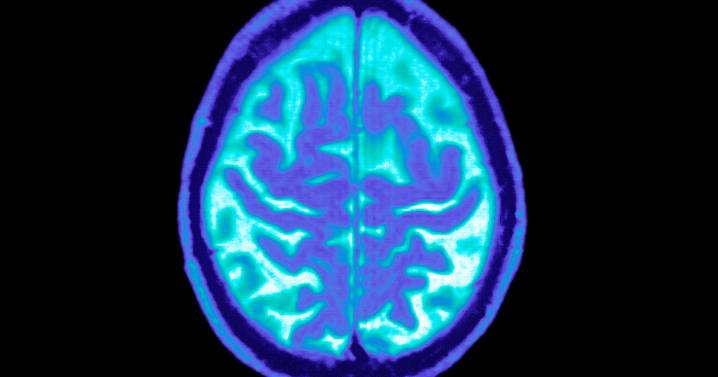

While GLP-1 drugs have become synonymous with dramatic weight loss, they’ve also become one of the most closely watched experimental approaches for slowing Alzheimer’s, a disease with few treatment options.

That’s why Novo Nordisk’s announcement last month that it discontinued two large trials — evoke and evoke+ — was viewed as a major setback for Alzheimer’s researchers and patient advocates.